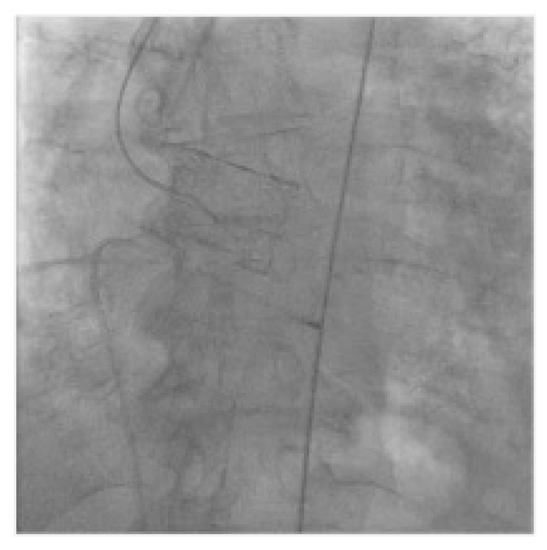

2.2. Technology

2.3. VIV-TAVR Planning and Technical Procedures